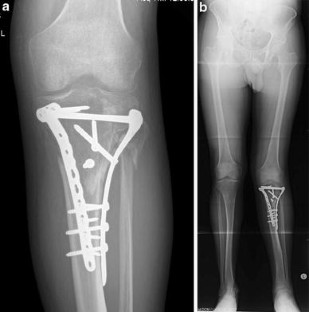

This study was conducted to examine the long-term survivorship and functional outcome of distal femoral varus osteotomy with fresh osteochondral allograft following failed lateral tibial plateau fracture surgery. We hypothesized that this procedure would be associated with a low rate of conversion to total knee arthroplasty (TKA) at medium to long-term follow-up.

A consecutive series of 27 of distal femoral varus osteotomy combined with fresh osteochondral allograft following (27 patients) conducted between January 1981 and January 2005 for failed lateral tibial plateau fracture was retrospectively reviewed. Outcome measures included the Knee Society Knee Score (KSKS) and Knee Society Function Score (KSFS) and conversion rates to TKA.

The study group consisted of 15 females (55.6 %) and 12 males (44.4 %), with a median age of 41.2 years (range 17–62 years). The median follow-up was 13.3 years (range 2–31 years). The knee function scores improved significantly at 2 years post-surgery (p < 0.01) from a median of 54.6 points preoperatively to 83.8 points (KSKS) and median of 50.6 points to 71.1 points (KSFS) at 2 years post-distal femoral varus osteotomy with fresh osteochondral allograft following surgery. At most recent follow-up, 4/27 patients had required conversion to TKA, and one patient had fractured the FOCA, requiring revision of the allograft. The survivorship for distal femoral varus osteotomy with fresh osteochondral allograft following was 88.9 ± 4.6 % at 10 years, 71.4 ± 18.1 % at 15 years, and 23.8 ± 11.1 % at 20 years.

The use of distal femoral varus osteotomy combined with fresh osteochondral allograft following in patients with failed lateral tibial plateau fracture results in the majority of patients having good or excellent clinical outcomes and significantly delays the need for TKA in most patients.